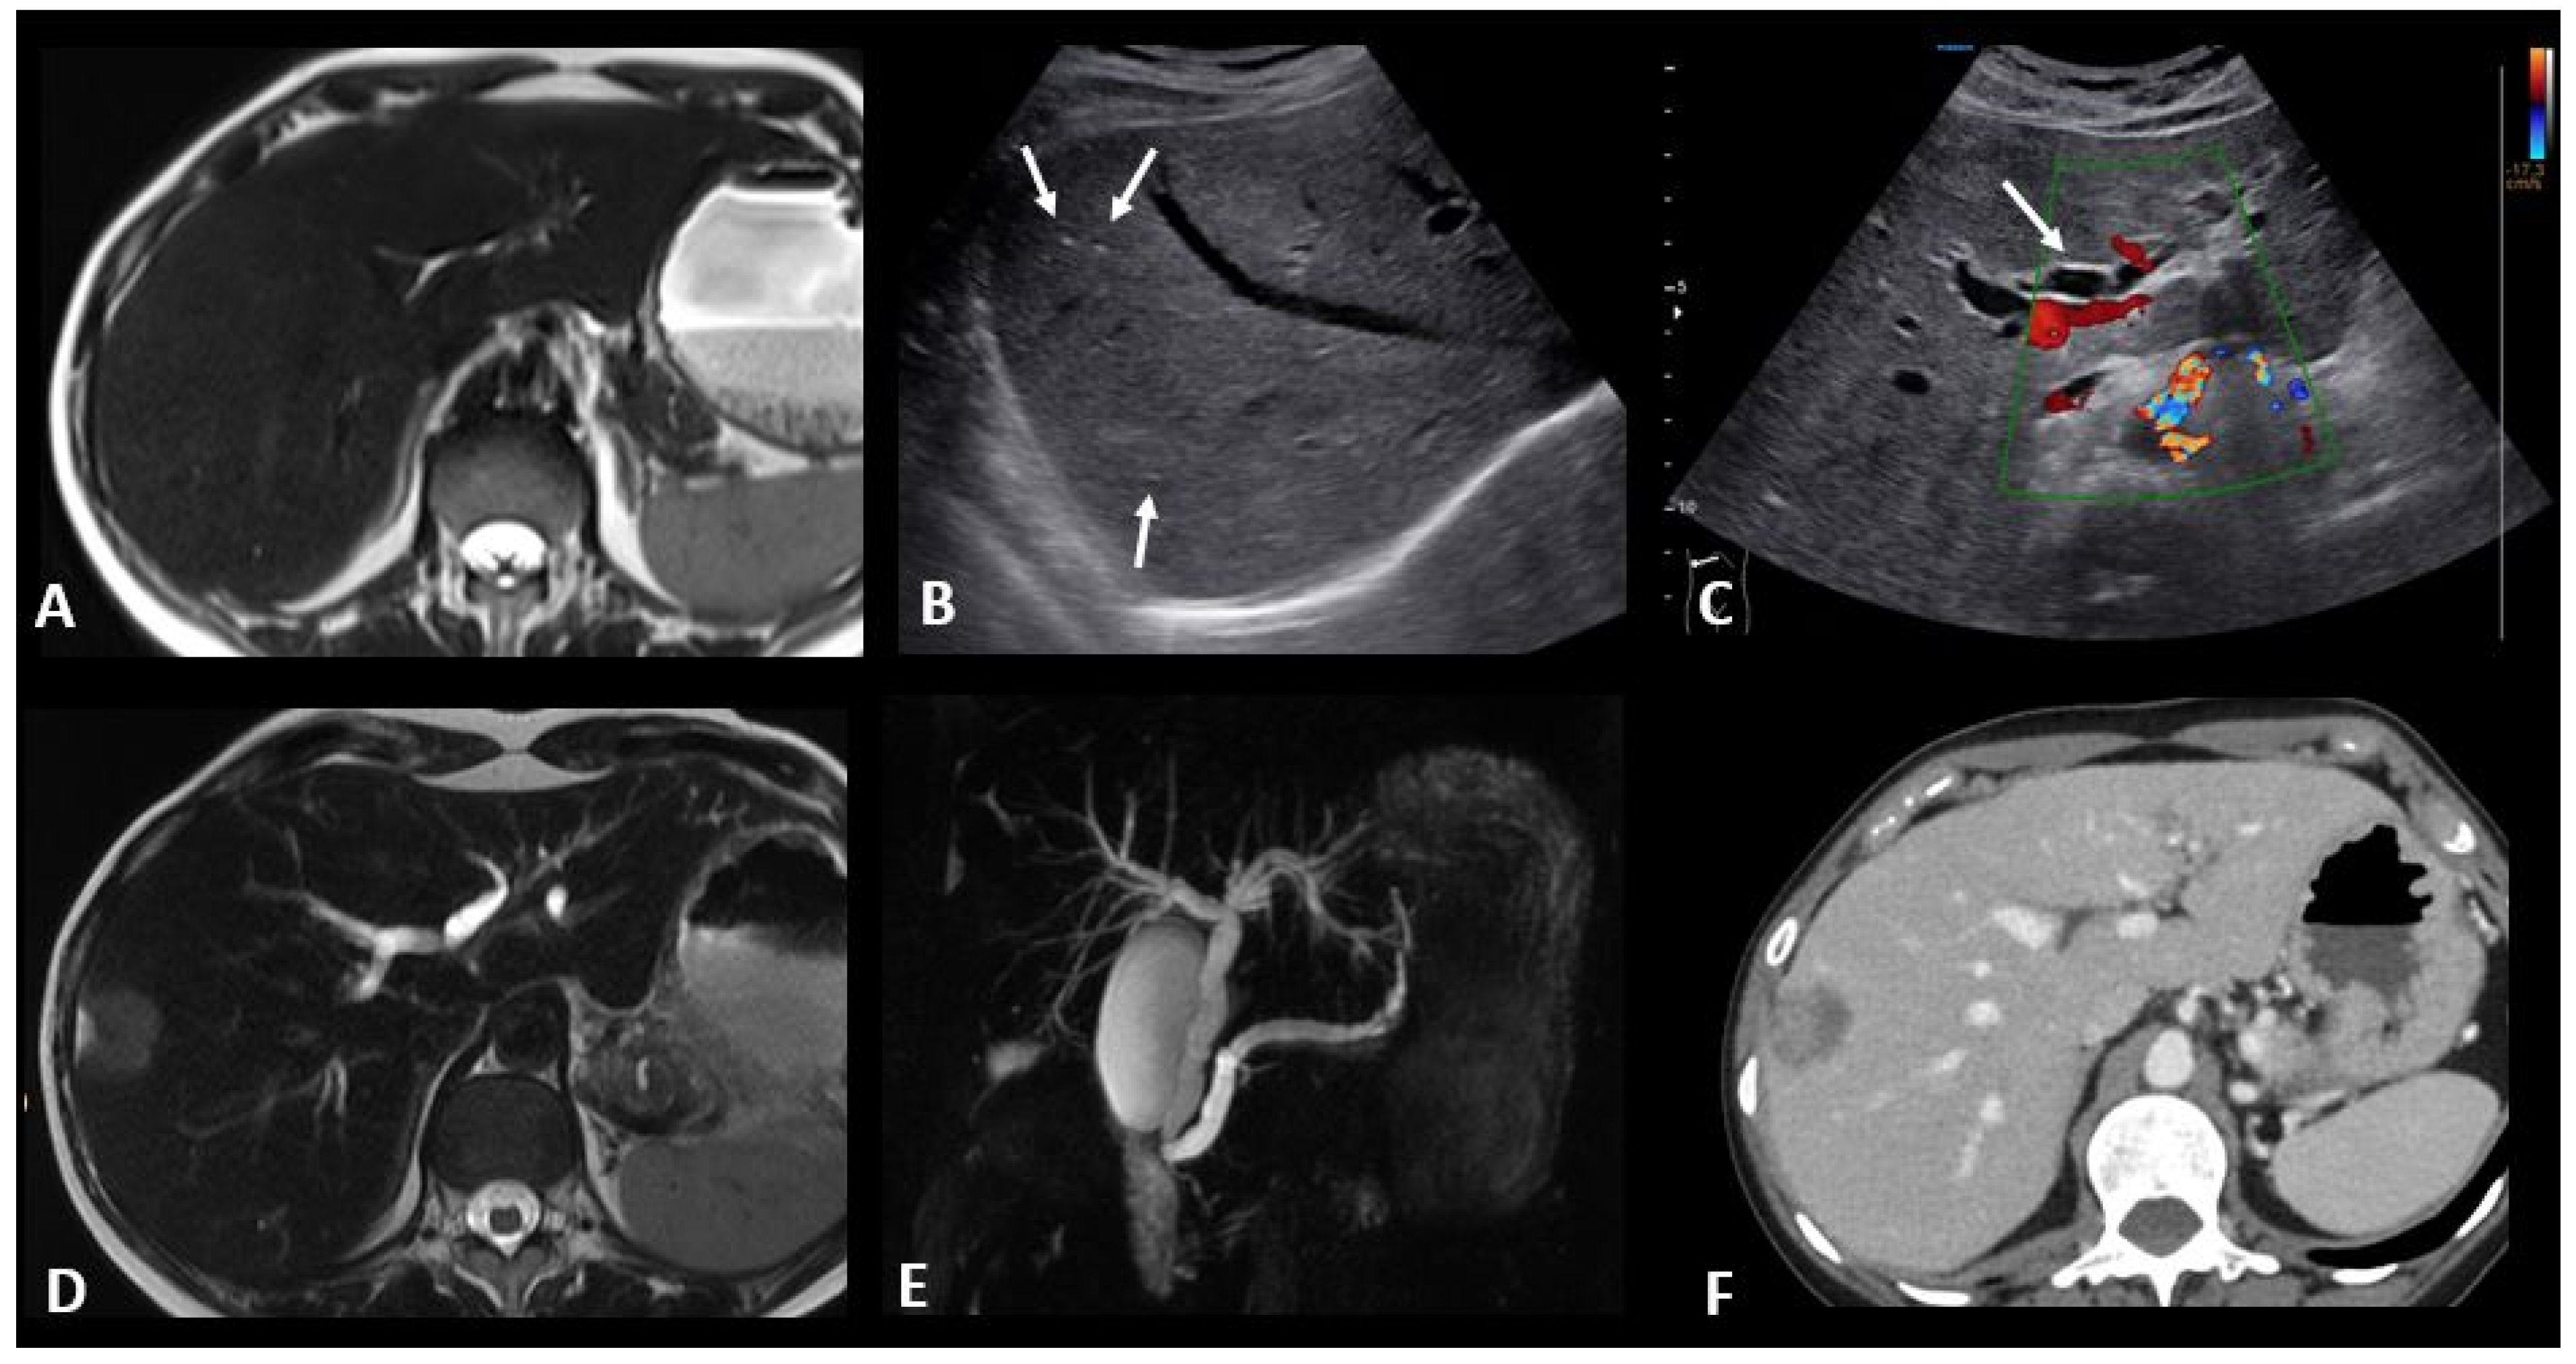

2.4.3. Ir-Hepatitis

2.4.4. Ir-Cholangitis

2.5. Ir-Endocrinopathies

2.5.1. Ir-Hypophysitis